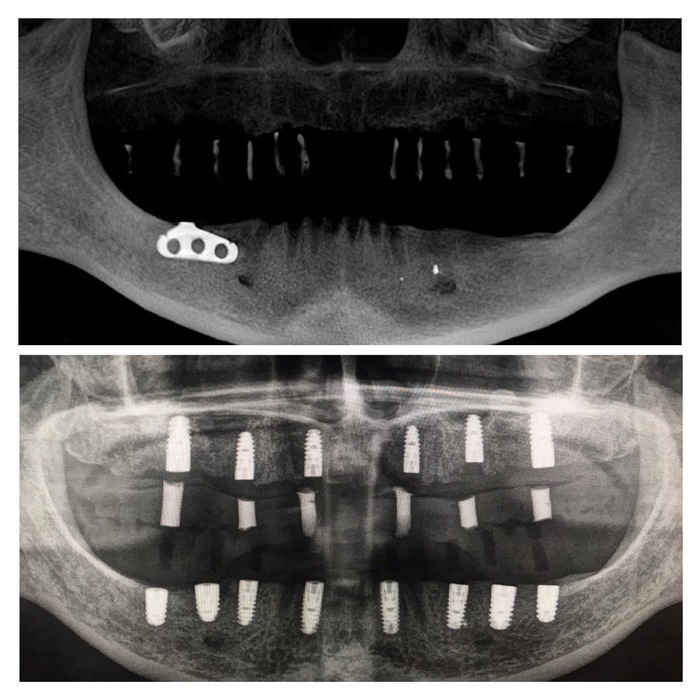

Вот один из примеров.

Пациентка достаточно трепетно относится к зубам. Как мы видим, она активно занималась лечением и восстановлением зубов. Но время идет, а следовательно, срок службы пломб, коронок и мостов подошел к концу. Кроме того, что портятся свои зубы, проблемы могут начаться и с установленными имплантатами, как в данном случае. Вторые также приходится удалять. Не говоря уже о том, что некоторые доктора до сих пор устанавливают пластиночные имплантаты без каких-либо показаний. Которые очень легко могут сломаться, как в данном случае. А все почему? Да потому, что не было комплексного подхода, плана лечения и видения ситуации. Вот скажите, зачем сюда "впихнули" тонкую пластину при такой ширине кости? А ведь наверняка перед операцией условия были еще лучше. Ну уж не хуже то точно.

Итак, после того как были учтены результаты диагностики, консультация ортопеда и, что немаловажно, пожелания пациента (!), было принято решение о удалении всех зубов на верхней и нижней челюсти, в том числе установленных ранее имплантатах. Кроме пластиночного, его я оставил на десерт.

На панорамном снимке ниже по середине четко видны контрастные "белые цилиндры", это как раз и есть тот самый материал, которым были закрыты отверстия в верхнем съемном протезе. Сам протез не рентгеноконтрастен, поэтому его на снимке не видно.

Ну и на десерт. Узрите! Вот оно, ТВАРЬение! Об этом я и говорил, пластиночный имплантат с отверстиями в нем, в которые проросла костная ткань. Ну и сломанный "штырь", который был одной из опор для мостовидного протеза.